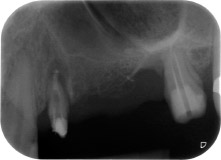

apikale Parodontalläsion an Zahn 24

Abb. 1: Bei einer 58-jährigen Patientin zeigt die Röntgenaufnahme vor der OP eine apikale Parodontalläsion an Zahn 24 und einen horizontalen Knochenabbau im zweiten Quadranten.

Eine 58-jährige Patientin, die auch eine gute Freundin und ärztliche Kollegin ist, beschwerte sich über Schmerzen und erhöhte Beweglichkeit ihres Brückenpfeilers 24. Es lag auch eine parodontale Entzündung vor, mit Taschentiefen von 7 mm mesiobukkal und mehr als 12 mm distal und einer Furkationsbeteiligung dritten Grades. Darüber hinaus zeigte die Röntgenaufnahme eine großflächige apikale Aufhellung am endodontisch (alio loco) vorbehandelten Zahn 24 (Abb. 1).

Ein Jahr zuvor waren die Zähne 25 und 26 vor dem Einsetzen der Brücke aufgrund traumatischer und endoparodontaler Ursachen extrahiert worden. Eine Paro-Endo-Läsion wurde bei unklarer ätiologischer Hauptkomponente für den Zahn 24 diagnostiziert. Die Patientin machte deutlich, dass sie ihre Pfeilerzähne 24 und 27 behalten und keinen endgültigen oder temporären herausnehmbaren Zahnersatz akzeptieren will. Darum wurde vereinbart, alles zu versuchen, beide Zähne, trotz der nach den radiologischen und klinischen Befunden als schlecht einzustufenden Prognose, zu erhalten.